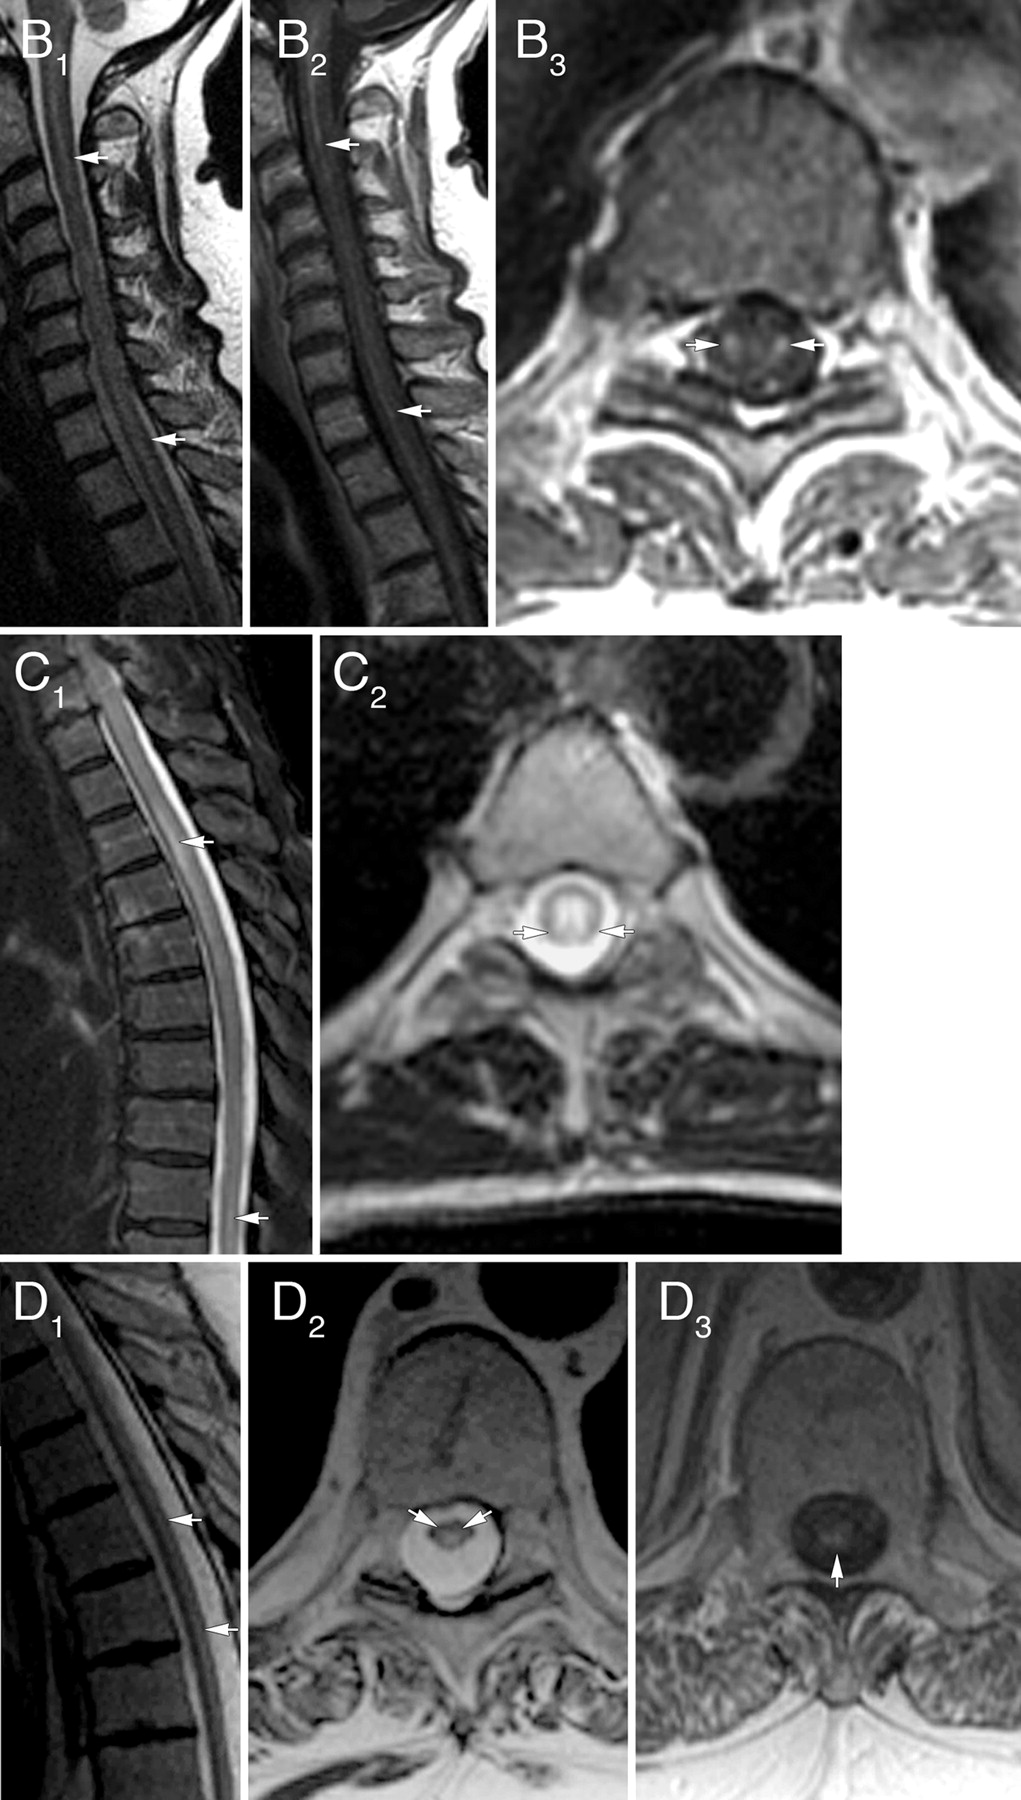

脊柱MRI(胸、颈,28日;颈,3)显示T2信号异常20例(65%)(图1和2)。14个病人纵向广泛的信号异常(> 3椎段;中位数6.5段)。15个患者对称和呼吸道或灰质在T2信号异常,在接下来的分布:侧列,5;脊柱,4;中央灰质,4;背侧柱,1;和脊柱和灰质,1。脊髓病变显示钆增强13(对称,8;不对称,5)。全身PET扫描,12例,揭示癌症3。 None had spinal cord hypermetabolic foci. MRI findings did not correlate with the cancer type or paraneoplastic autoantibody. Brain MRI performed in 26 patients showed no lesions typical of MS.

尽管三分之一的患者有正常的脊柱MRI, 48%有对称的小说发现脊髓信号异常。片状钆增强报道的坏死性多种患者脊髓病,18但从我们的研究作为一个新兴的主导模式的特征多种的脊髓病是对称纵向广泛T2信号束/灰质分布异常,经常表现出对称的增强。两个类似的患者MRI发现先前文献中均有描述。1,19某些情况下表现出异常信号的模式类似于其他疾病。“猫头鹰眼”或“蛇眼”模式的T2 hyperintensity据报道在缺血性脊髓炎20.,21(预计有急性发作)。视Neuromyelitis典型纵向广泛脊髓炎,但偏爱中央灰质和钆增强而不是对称的通常是不完整的。22它还可以很少有“猫头鹰眼”或“蛇眼”外观。22所有病例在这项研究是AQP4抗体阴性。Tract-specific T2信号变化描述的维生素B12缺乏症23和肌萎缩性脊髓侧索硬化症24通常不与钆增强,临床和实验室特征排除诊断。排除了癌症转移性脊髓没有离散结节病灶实质钆增强,软膜的增强,或在PET成像hypermetabolic疫源地。25,- - - - - -,27神经通常是与leptomeningeal增强有关。28